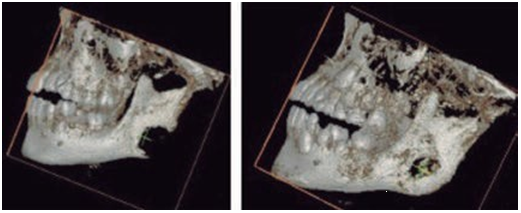

Based on the clinical data and medical history, the maxillofacial surgeon indicated a lateral skull radiograph (Figure 2), where atypical bone lysis was observed according to the age of the patient. Then a computed tomography was requested to determine the limits and three- dimensional characteristics of the lesion, where cortical expansion with bone lysis was observed Figure 3), which led to a presumptive diagnosis of a malignant tumor in the mandibular angle to be determined, also laboratory tests were requested showing increased levels of alkaline phosphatase (212 U/l), serum phosphatase (6.9 mg/dl) and serum calcium (10.7 g/dl). According to clinical, imaging and laboratory examination, the maxillo- facial surgeon performed incisional biopsy in June of 2019. The patient underwent general anesthesia with orotracheal intubation, carried out via an intraoral approach with an incision in the left anterior border of the mandible branch dissecting to the mandibular angle of the external fase and performing an ostectomy with a low-speed handpiece at the site of the lesion, bone tissue was obtained for histopathological analysis.